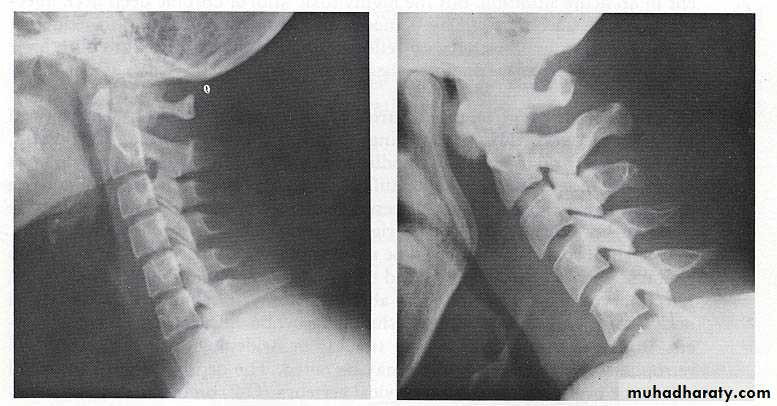

Imaging:

Lateral neck plain film

Screening examNo benefit in pts with DNI based on strong clinical suspicion.

Normal:

7mm at C-2

14mm at C-6 for kids

22mm at C-6 for adults

Technique dependent

Extension

Inspiration

Sensitivity 83%, compared to CT 100%